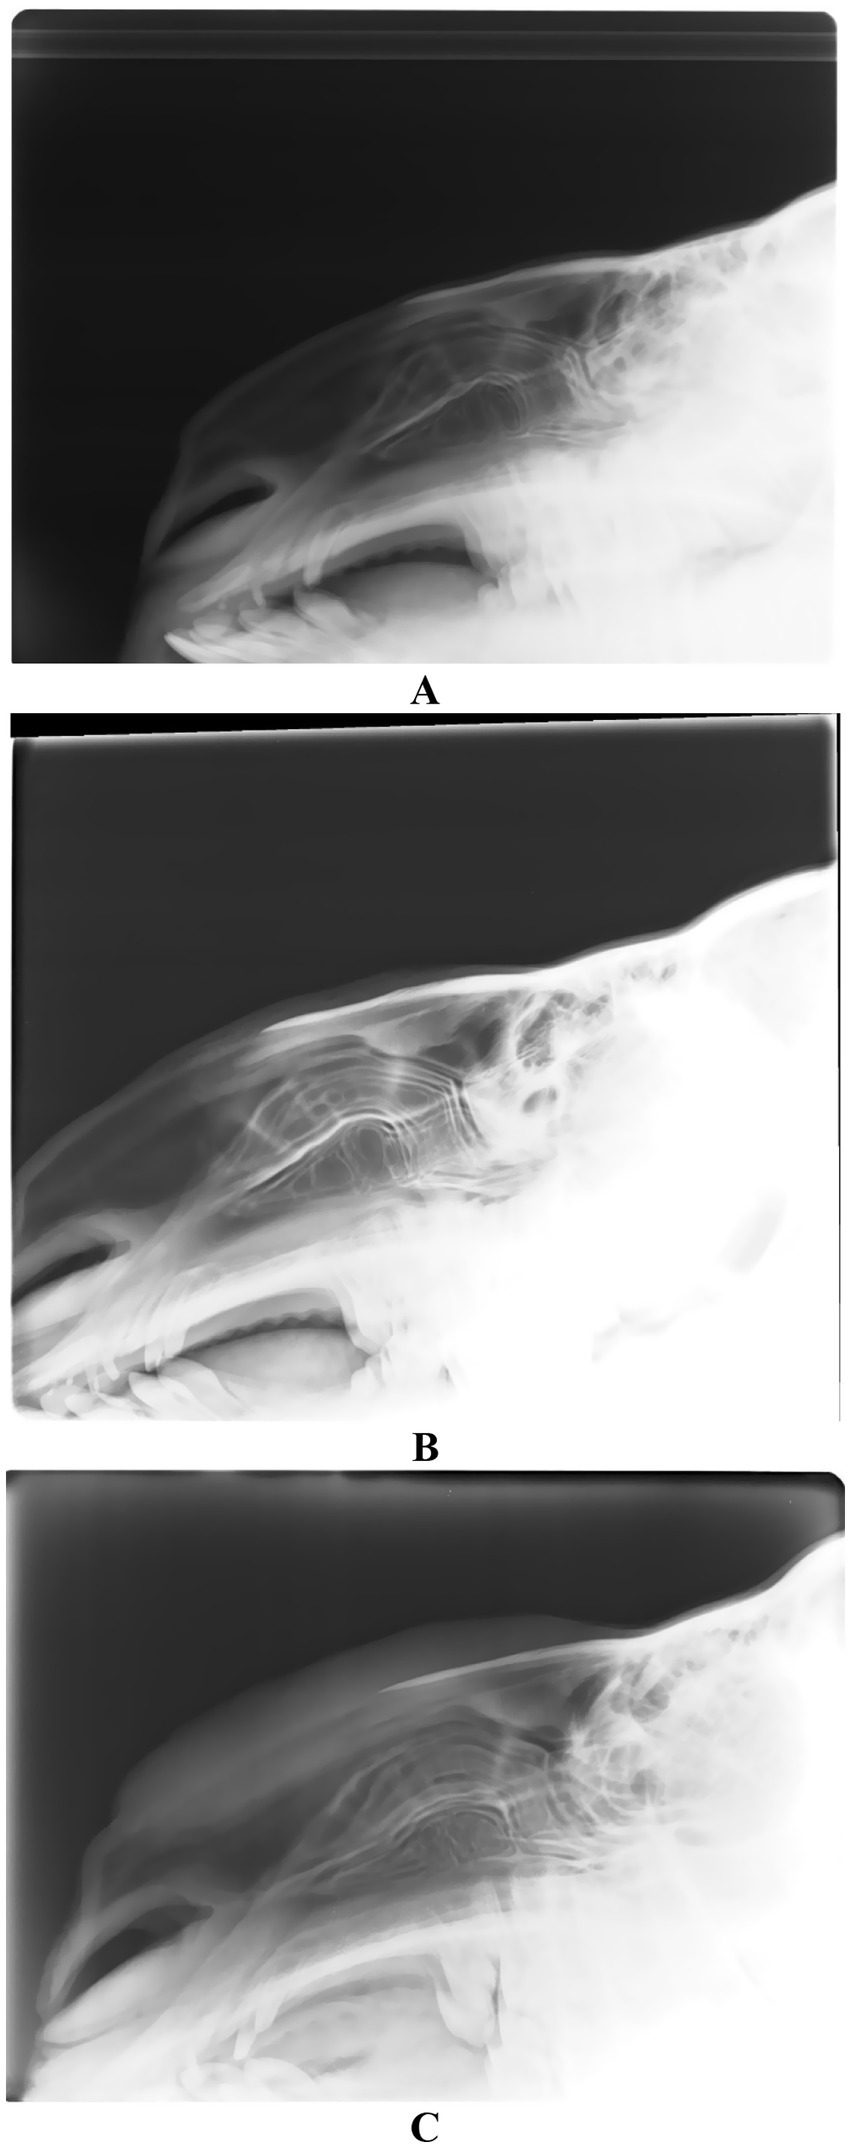

Radiographic evaluation of camels administered cosmetic fillers in the perinasal area demonstrated varying degrees of soft tissue enlargement. This was attributed to the injection of moderate to substantial volumes of filler material both anterior and posterior to the nasal bone (14). Notably, there were no observable alterations in the nasal bones or cartilage when compared to non-injected, clinically healthy camels. The filler material appeared as a soft-tissue density, presenting a gray tone on radiographic imaging within the perinasal region (14) (Figure 9).

Figure 9

Lateral radiographic view of 3 camels injected with perinasal region fillers. Image (A) shows a healthy camel with no injections. Images (B,C) show camels with moderate and large quantities of filler injection, respectively. Please not the swelling of the surrounding soft tissues anterior and posterior to the nasal cartilage [Reproduced from (14)].